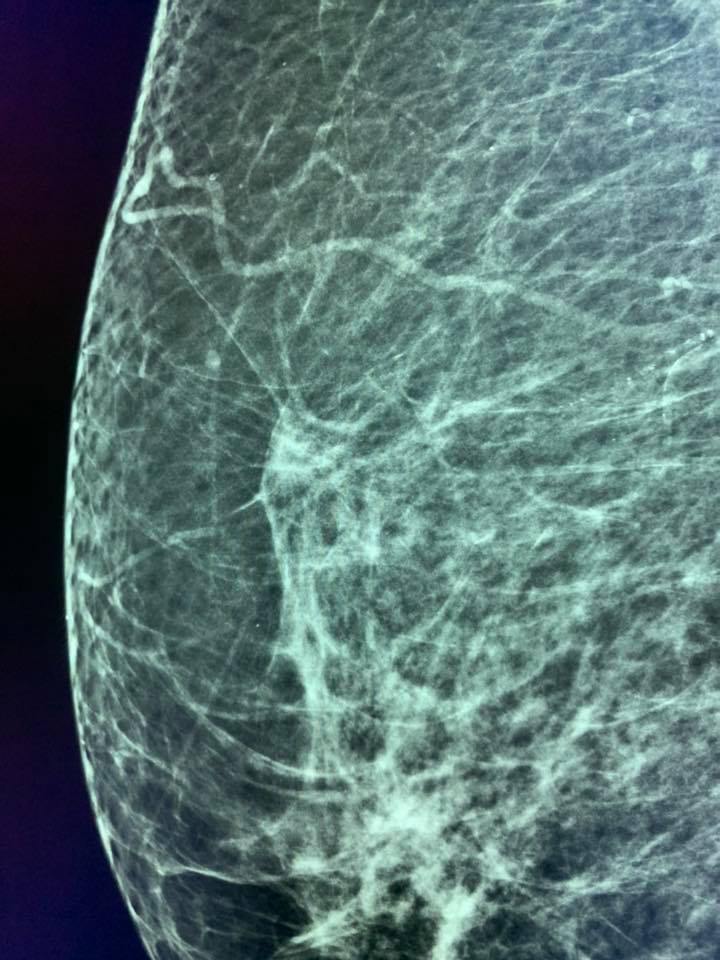

Une femme de 73 ans, mammographie de dépistage. Deux ans avant, sa mammographie de dépistage était considérée comme normale par deux lecteurs.

À première vue, la nouvelle mammographie mammaire a également été considérée comme normale et inchangée par rapport à la précédente, mais MammoScreen a mis en évidence une lésion sur le sein droit.

L’analyse rétrospective de la précédente par MammoScreen a montré la même zone.

L’IRM a mis en évidence une masse spiculée sur le sein droit.

A première vue, ma collègue n’a pas réussi à trouver la lésion avec l’échographie et a essayé deux fois la macrobiopsie sans succès.

Finalement, un autre collègue a réussi à la localiser grâce à l’échographie et a effectué une microbiopsie guidée par l’échographie. Carcinome mammaire invasif de type luminal A.